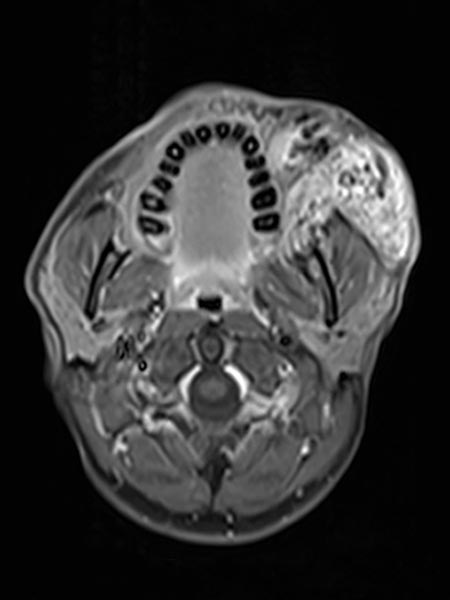

Axial, T2-weighted MRI at the level of the cheek shows the AVM to be relatively hyperintense with edema of the surrounding tissue and extension to the left mandible. In the rostral section some black flow voids are visible as a sign of arteries with fast flow within the AVM.

Inhomogeneous, peripheral enhancement of the proliferating AVM in this axial fat-suppressed T1-weighted MRI after contrast administration. No circumscribed component that is actually solid, unlike in a true vascular tumor.